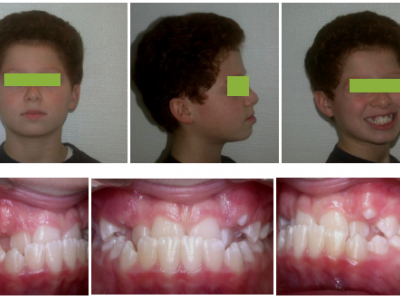

- Le second cas est un enfant de 6 ans 4 mois consultant pour une prognathie mandibulaire (Fig. 10).

La mandibule circonscrit le maxillaire en avant et vers la droite. Comme le maxillaire est inscrit dans la mandibule à droite avant tout contact prématuré générant une déviation, le décalage transversal est déjà visible sur la photo de face, en position de repos. Le sourire découvre les dents inférieures, et s’apparente à un rictus. L’occlusion montre une endognathie et une rétrognathie maxillaire avec prognathie et latérognathie mandibulaire droite.

La projection mandibulaire est toujours plus marquée sur la téléradiographie qui est en occlusion (Fig. 11-16), que sur la photo, en position de repos, donc en inocclusion, avec une situation un peu plus reculée de la mandibule. Sur la radiographie panoramique, le manque de place est plus important à l’arcade supérieure, témoignant du manque de développement de cette structure. L’expansion tridimensionnelle de l’arcade donnera de la place aux dents permanentes.

- Le traitement du deuxième cas a commencé par un appareil à plans molaires d’une hauteur importante, pour une expansion transversale et antérieure du maxillaire. Grâce à cette surélévation de l’occlusion, le surplomb maxillaire est obtenu, un élastique de classe III est mis à gauche pour aider le recentrage.

Quand les dents supérieures recouvrent les inférieures (Fig. 12), la hauteur des cales est progressivement diminuée pour ne pas laisser de béance latérale. Les incisives centrales maxillaires sont rapprochées pour donner la place aux latérales, et les brackets mandibulaires améliorent le recouvrement et la position des incisives inférieures. Sur la photo, les cales ont déjà été diminuées (Fig. 12) de plus de la moitié de leur hauteur efficace de départ.

Les bagues et l’appareil sont ôtés 3 mois plus tard (Fig. 13), en juin, pour les vacances d’été, puis le patient est revu à la rentrée de septembre (Fig. 14).

Pour le second cas, on note que grâce au traitement, le visage a retrouvé une harmonie et une symétrie.

Après traitement le patient ne sourit plus avec les dents inférieures, mais avec les incisives supérieures (Fig. 13).

La plaquet à surélévations a permis le repositionnement correct du maxillaire par-dessus la mandibule, et des attaches collées antérieurement ont aligné les dents. Le manque de place pour les dents définitives s’est spontanément amendé (Fig. 14).

Le patient est revu en denture définitive à 12 ans 9 mois (Fig. 15) avec un bilan radiologique (Fig. 16), pour entreprendre une finition multiattache, les résultats orthopédiques obtenus précocement se sont maintenus.